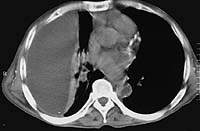

Рентген опухолей плевры: диагностика и лечение